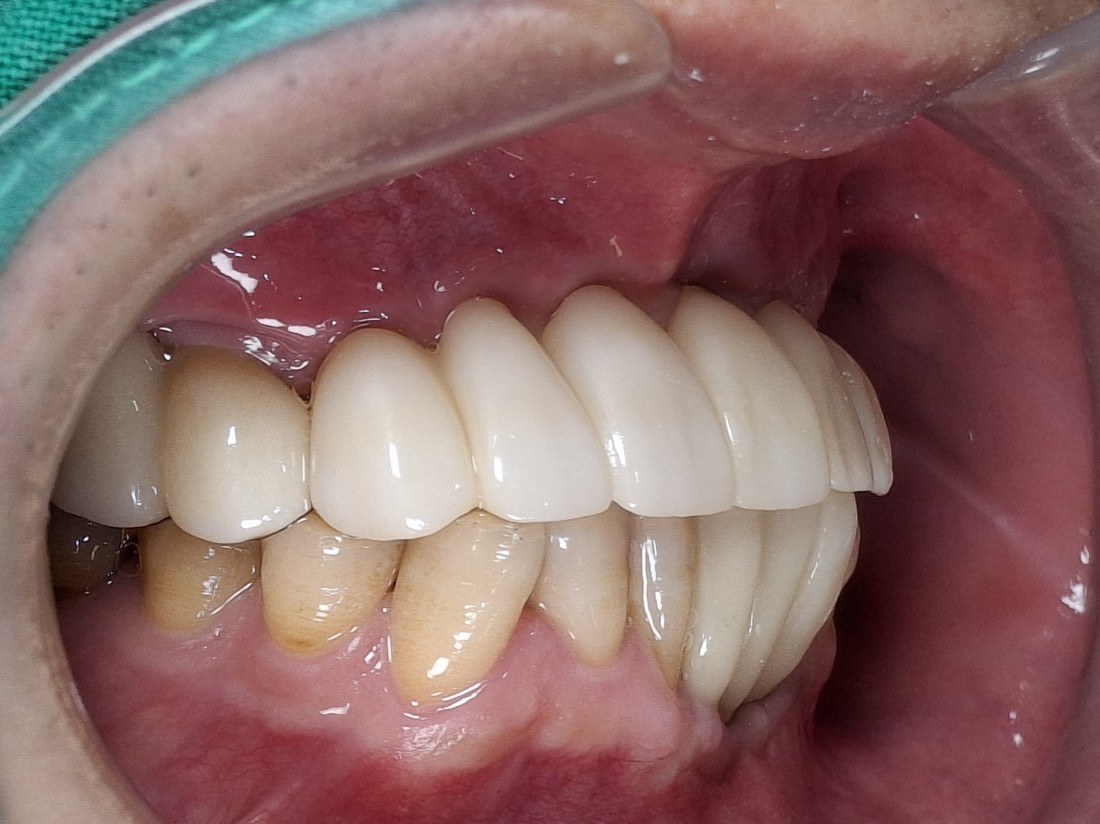

임플란트 수술 후에 통증이 매우 심한 경우는

잇몸절개를 많이 했을 확률이 높습니다.

전남광주 임플란트치과에서는

잇몸절개를 하지 않고 무절개로 하거나,

최소한으로만 절개하는

디지털 가이드 임플란트 수술을 하기 때문에

임플란트 수술 후에

붓기, 출혈, 통증이 매우 적습니다.